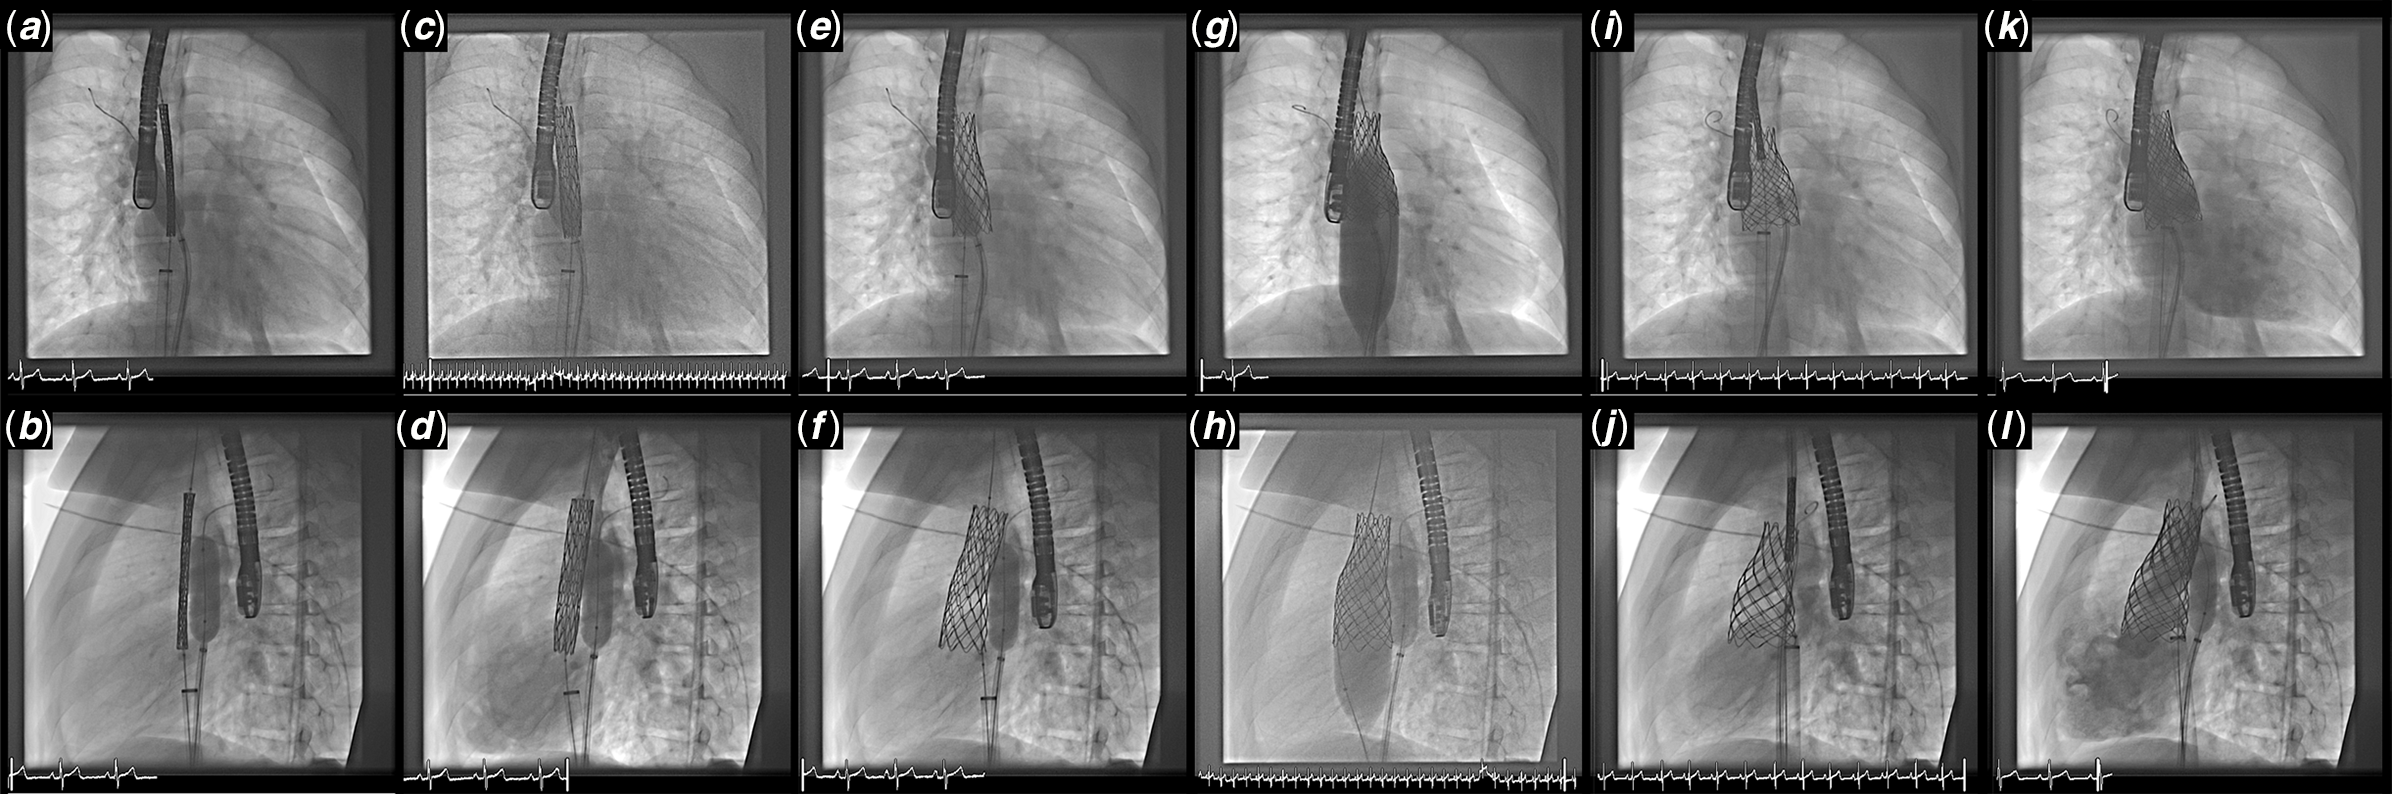

Although the surgical repair of this defect remains the gold standard, in recent years transcatheter closure has become an option in a select group of patients. In 2014, Garg et al. Reference Garg, Tyagi and Radha26 reported a transcatheter closure of sinus venosus defect in a patient with bilateral superior caval veins, using a covered stent in the superior caval vein to close the defect and redirect the right upper pulmonary vein flow around the stent into the left atrium. With meticulous pre-procedural planning using balloon interrogation, Reference Garg, Tyagi and Radha26–Reference Abdullah, Alsalkhi and Khalid28 three-dimensional printed models, Reference Velasco Forte, Byrne and Valverde25,Reference Riahi, Velasco Forte and Byrne29,Reference Hansen, Duong and Jivanji30 image fusion guidance Reference Thakkar, Chinnadurai, Breinholt and Lin31 or even holographic augmented reality, Reference Butera, Sturla, Pluchinotta, Caimi and Carminati32 these initial reports have demonstrated the feasibility and safety of transcatheter closure of sinus venosus defect in these patients in short to medium term (Fig 7). The transcatheter approach however may not be suitable in patients with right upper pulmonary vein that connects to high right superior caval vein or a relatively hypoplastic right superior caval vein especially in the presence of bilateral superior caval veins due to the risk of pulmonary venous obstruction by the covered stent. Reference Riahi, Velasco Forte and Byrne29

Figure 7. This series of angiography images show the steps in using a covered stent to repair a sinus venosus defect. ( a and b ) Anteroposterior (AP) and lateral views of a un-expanded 7 cm long 10-Zig covered CP stent mounted on a 28 mm BIB and introduced on a veno-venous guide wire rail and a separate pulmonary vein protection balloon (14 mm Atlas Gold balloon); ( c and d ) The inner balloon of a 28 mm 8 cm long BIB is expanded and the position adjusted on TOE imaging to overlap the crest of atrial septum; ( e and f ) The stent is further expanded by inflating the outer balloon; ( g and h ) Further flaring of the lower half of the stent is performed until the stent abuts the septum and there is no or minimal residual shunt on TOE. (h and i) An un-expanded bare-metal anchor stent and (k and l) post-expanded bare-metal anchor stent is the place to secure the flared conical Covered CP stent. The pulmonary vein is protected throughout by keeping the high pressure balloon inflated inside the pulmonary vein whenever the covered stent is dilated.